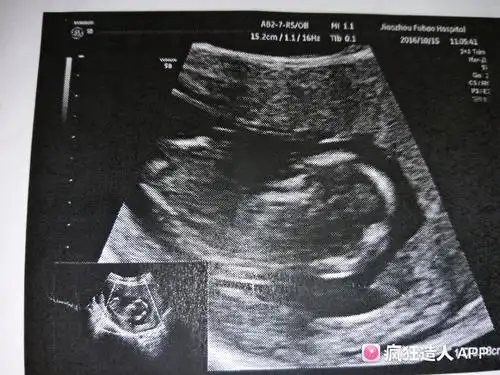

检查,通过每一次的检查,医生可以很准确的查看出胎儿在腹中的发育状态

13周nt归来,有没有懂nub理论的姐妹帮看男女呢?

b超可以看出胎儿的性别

nt看男女有85%的准确率

热乎乎的nt秒过会看男女吗